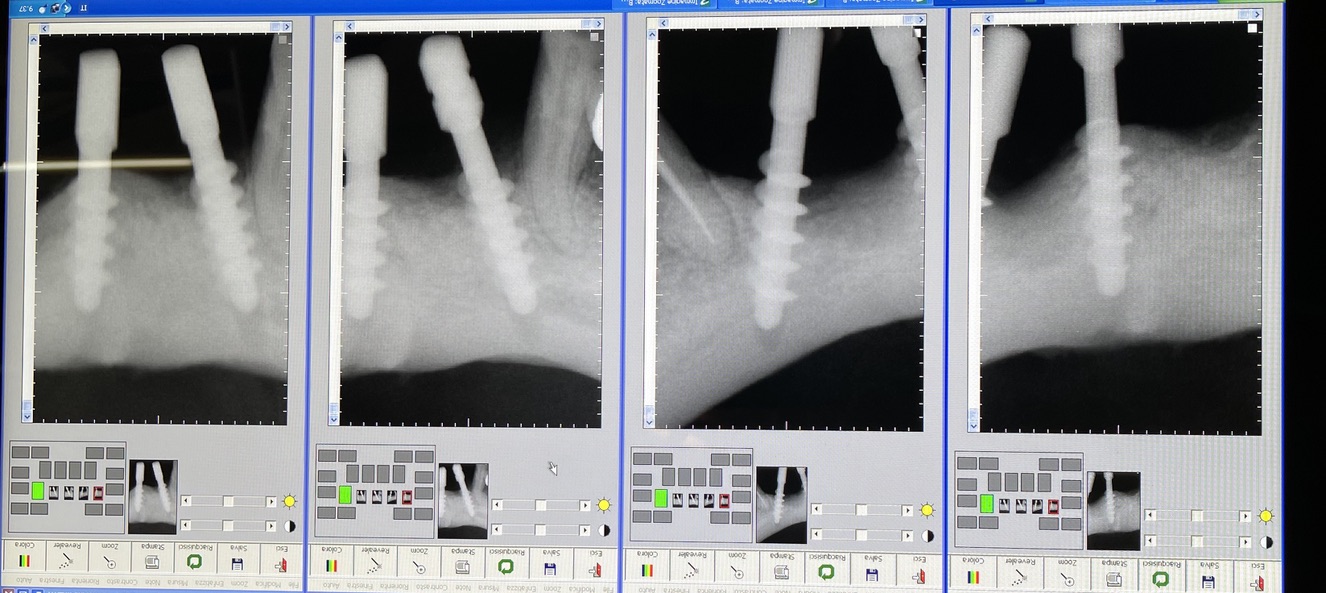

CASO CLINICO : Riabilitazione del 28/04/2021

In particolare considero notevoli i seguenti aspetti:

• 2 esecuzione dei primi 6 impianti: 25 anni fa

• 3 esecuzione dei 5 impianti successivi: 14 anni fa

• 5 presenza di impianti in zona tuber/pterigoidea

• 6 presenza di impianti inclinati di antica data

• 7 presenza di impianto piegato in 25. (Per parallelizzarlo)

• 16 Trattandosi di osso ad elevata densità si è ricorsi alla fresa elicoidale, strumento raramente utilizzato da noi perchè non necessario e perchè ci sono zone in cui il suo utilizzo comporta rischi chirurgici per noi non accettabili. Inoltre questa fresa asporta quantità discrete di osso che preferiamo resti dove la natura lo ha messo. Interessante il fatto che il diametro della fresa è di solo 2 mm

• 17 Trattandosi di osso denso, gli impianti utilizzati avevano un diametro di soli 4 mm dopo maschiatura col corrispondente maschiatore.

Le immagini forniscono nelle didascalie ulteriori informazioni.